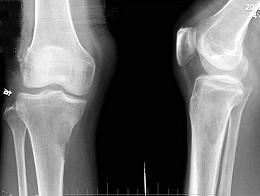

问题 男,59岁,右小腿近端疼痛1年,活动障碍半年,结合图像,最可能的诊断是?(?)

选项 A.右胫骨结核 B.右胫骨骨转移 C.软骨肉瘤 D.骨肉瘤 E.纤维肉瘤

答案 B